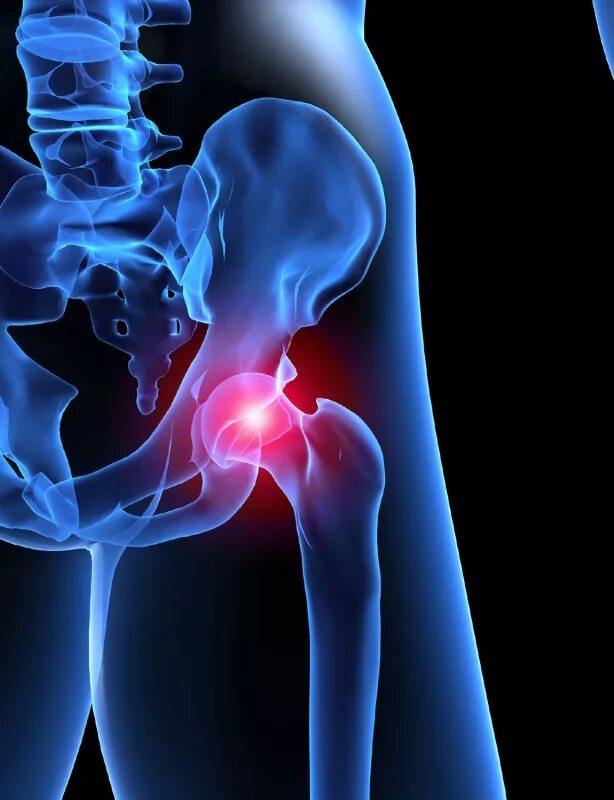

Как лечить синовит тазобедренного сустава